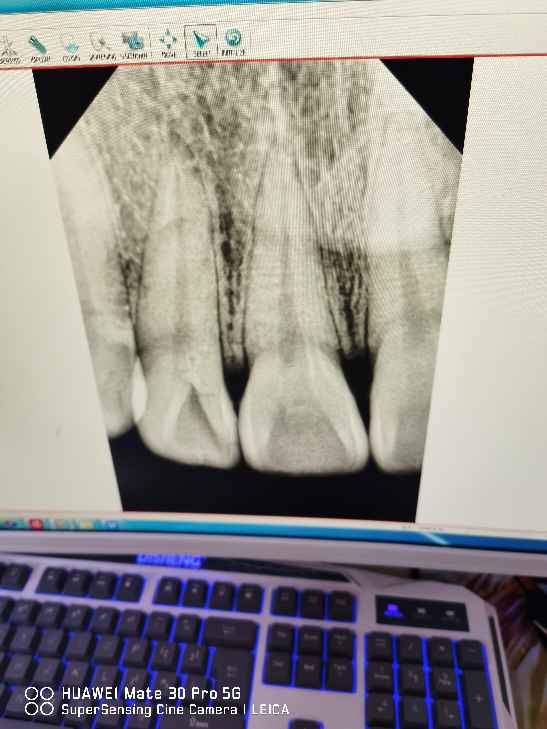

最近牙齿内部有点黑,去医院拍了一个片子,说可能是牙周炎要补牙,甚至根管治疗,不太相信,烦请各位大佬帮忙看一下,谢谢。 @carci 发自小木虫Android客户端 |